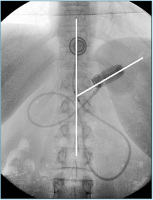

LAGB

Abbildung 2: Normalbefund nach LAGB: Das Band bildet mit der Längsachse der Wirbelsäule einen Winkel von knapp 50° (Normalwert von 5–60°).

Keywords: GastroenterologieMagenbandRadiologie